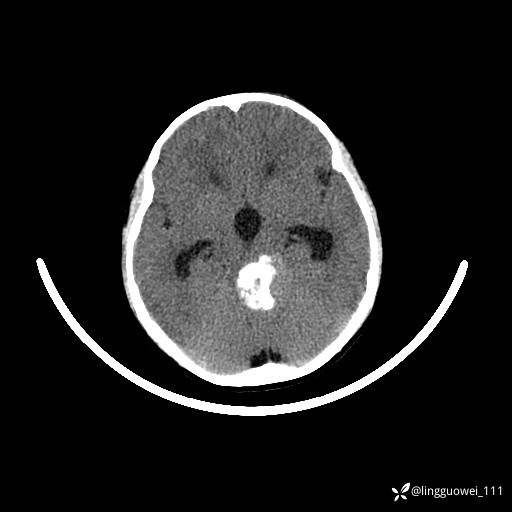

男,8岁,外伤后发现颅内占位,定位定性,4天后公布结果。

患者性别:男

患者年龄:8岁。

主诉:外伤后发现颅内占位。

外院做的手术,术后回本院复查,只有平扫,定位在哪?良性还是恶性?